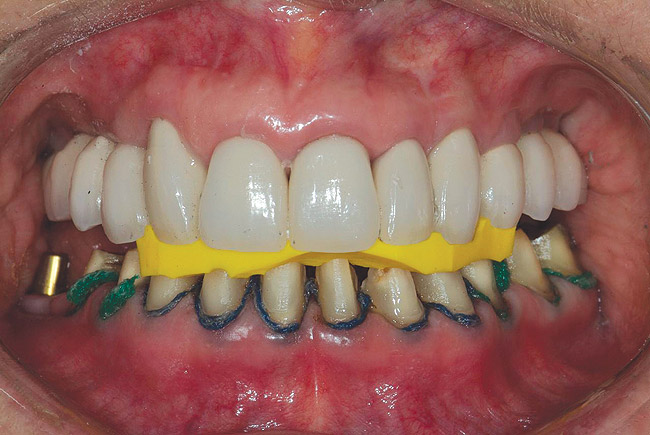

Figure 4  Interocclusal registration made at the approximate OVD for rehabilitation.

Figure 4

The registration of the transverse hinge axis and transfer with a facebow simply serves to locate the maxillary cast on the articulator. An accurate registration of centric relation allows the laboratory to mount the mandibular cast in a repeatable position for the purposes of reconstruction.18 Commonly, interocclusal records provided to the laboratory are with teeth in contact or the laboratory is asked to hand-articulate without the benefit of a bite registration. Besides a lack of repeatability, casts mounted in contact must be separated to a working vertical dimension. Because the earbow/facebow mounting is an arbitrary positioning of the maxilla, the casts will routinely not be on the same arc of closure as found intraorally. This means that as the casts are separated there is the possibility of a significant anterior–posterior shift.19 The error compounds the farther from the true hinge axis the facebow was fabricated and the greater the casts are opened on the arbitrary arc. Because of this magnifying error, Gracis suggests that interocclusal records should be fabricated at the vertical dimension that they will be rehabilitated.19 Dentists should visualize the ideal incisal edge position of the maxillary incisors and their ability to couple at the proposed vertical. Evaluating the patient’s central incisor display in repose and full smile arrives at this position.17 The author then uses a leaf gauge to separate the anterior teeth enough to accommodate the additional length (Figure 3 through Figure 5). The leaf gauge has the additional benefit of allowing the interocclusal registration to be fabricated with a seated condyle. This is obviously an arbitrary choice. The laboratory technician will alter the position during the diagnostic wax-up. Due to the fact that the registration is fabricated in an open relationship, the amount of modification in the OVD on the articulator will be significantly less. This will minimize the error found in wax-ups fabricated from a closed interocclusal record.